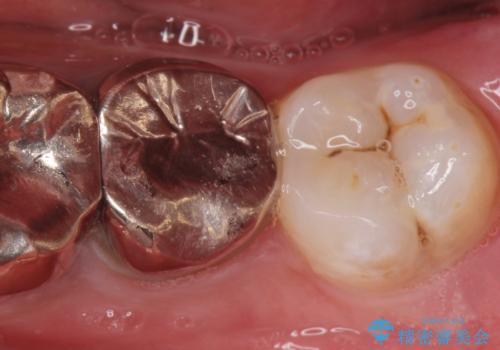

- 今後奥の歯の治療を行う患者様です。

親知らずが生えていましたので治療を始める前に親知らずの抜歯を行いました。

左上下2本抜歯を行いました。

親知らずは汚れが溜まりやすく。手前の歯が虫歯になるリスクが高いため早期に親知らず抜歯をする事をお勧めします。